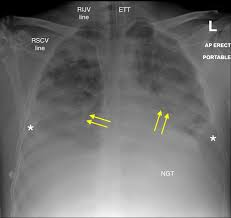

• ARDS

rapid onset of widespread inflammation in the lungs

provoked by an acute injury to the lunfs that results in flooding of the alveoli

looks like ground glass in imaging

causes - pneumonia, aspiration, inhalational lung injury, lung contusion, chest trauma, spesis...